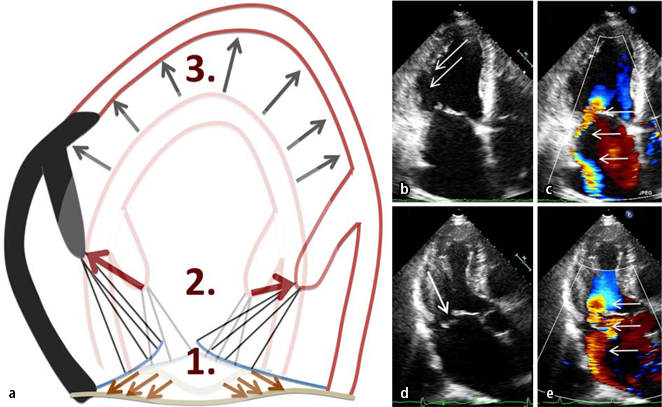

Ischamische Mitralklappeninsuffizienz Springerlink